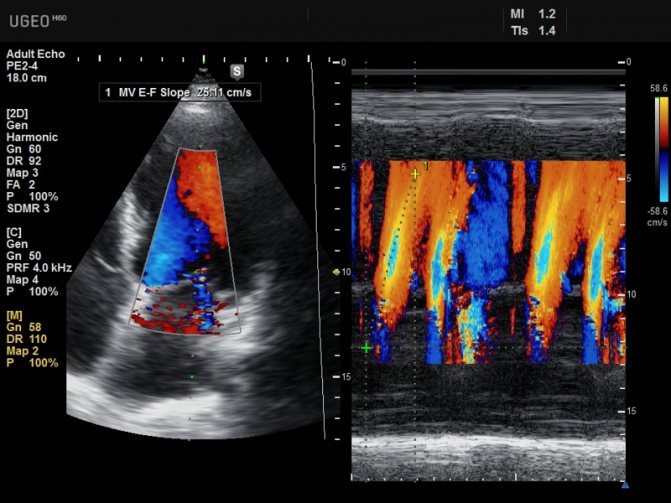

Последним нововведением в данной отрасли стало применение эффекта Доплера, названного в честь своего создателя, и УЗИ сердца дополнилось его возможностями. Эхокардиография с допплеровским анализом позволяет оценить не только анатомические особенности органа, но и основные характеристики кровотока в нем и близлежащих сосудах, что дает врачам максимум информации.

С помощью допплеровской эхокардиографии определяют скорость кровотока и его турбулентность. Когда звук сталкивается с движущимися эритроцитами, изменяется частота отражённого сигнала. Величина этого изменения указывает на скорость кровотока. Её рассчитывают, учитывая определённые характеристики звукового луча. Увеличение частоты отражённого звука вверх указывает на то, что ток крови направлен к датчику, а направление сдвига вниз, что от датчика. При прохождении крови через суженные отверстия клапанов её скорость увеличивается. Это также регистрируют с помощью эхокардиографии с допплеровским анализом.

Регистрация сигналов в отдельных небольших областях позволяет определить пространственную локализацию турбулентности, которая характерна для недостаточности, сужения клапанов или шунтирования крови. Сочетание допплеровского исследования с методами получения изображения позволяет рассчитать сердечный выброс. Не всем пациентам можно успешно выполнить эхокардиографию. Проникновение звука в ткани затруднено у многих лиц пожилого возраста, которые страдают эмфиземой и ожирением.

Эхокардиография с допплеровским анализом. Метод допплер ЭхоКГ проводится для определения скорости, с которой движется кровь и турбулентности кровотока. Информационные данные, которые получаются во время проведения, несут сообщение о пороках сердца и наполнении левого желудка.

Расчёт скорости объекта и её изменения, а также разницы частот сигналов являются основой данного способа проверки. Частота меняется, когда эритроциты сталкиваются со звуком. Допплеровским сдвигом обозначают объём этой перемены. Данный сигнал может восприниматься ухом человека и его можно воспроизвести при помощи эхо-аппарата в виде звука, который мы сможем услышать.

Эхокардиография, которая совмещена с допплерографией, позволяет получить показатели кардиогемодинамики и выявить патологии сердечной мышцы. При использовании цветного доплеровского картирования (ЦДК) удается увидеть патологические забросы крови в левое предсердие прямо во время сканирования.

- Допплер с цветным картированием. В зависимости от скорости направления движения эритроцитов поток крови подсвечивается каждый своим цветом. Поток направляется к датчику — красный, синий — от датчика. С помощью этого метода оценивается изменение скорости кровотока.